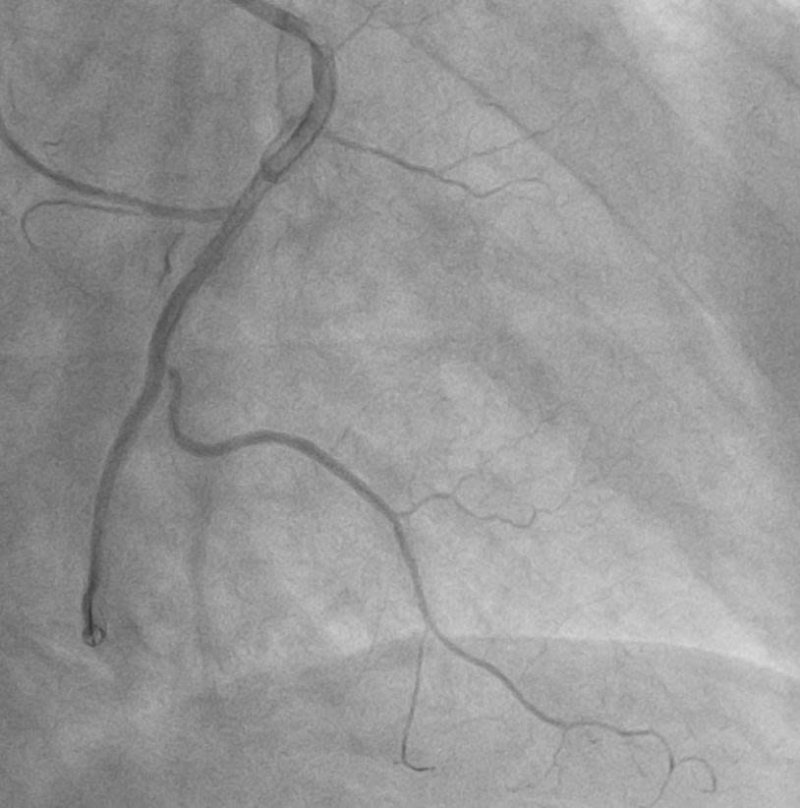

Ngay lập tức, bệnh nhân được kích hoạt quy trình cấp cứu tim mạch và chuyển tới phòng can thiệp mạch vành khẩn cấp. Kết quả chụp mạch vành cho thấy bệnh nhân bị tắc hoàn toàn động mạch vành phải đoạn 2 (RCA 2). Đáng chú ý, động mạch vành phải của bệnh nhân có vị trí xuất phát bất thường từ xoang vành trái của động mạch chủ – một dạng dị dạng hiếm gặp khiến việc tiếp cận và can thiệp trở nên phức tạp hơn nhiều so với các trường hợp thông thường.

Hình ảnh: Trước can thiệp